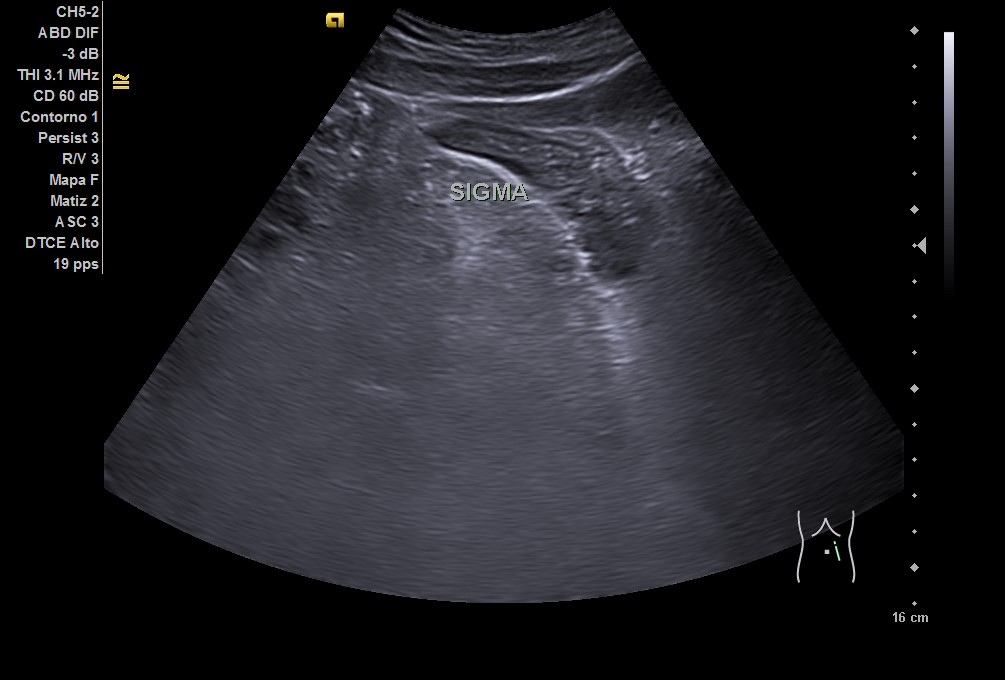

En ecografía clínica: hígado homogéneo sin lesiones, vesícula biliar sin litiasis. Riñones de forma, tamaño y ecoestructura normales. Arteria aorta sin dilataciones. Vejiga levemente repleccionada, ausencia de líquido libre en fondo de Douglas. Asa de sigma con posible edema de pared. Ante la clínica y los hallazgos ecográficos, se remite a urgencias del hospital de referencia.

• En urgencias, de inicio se realiza radiografía abdominal sin datos de obstrucción intestinal. Ante persistencia de dolor intenso, leucocitosis y aumento de PCR en analítica, se repite la ecografía (utilizando también sonda lineal) con hallazgo de diverticulitis aguda sigmoidea con datos de peritonitis regional pélvica, y posteriormente se realiza un TC abdominal con conclusión de diverticulitis aguda con pequeños abscesos murales, perforación de un divertículo y peritonitis pélvica.

La ecografía puede ser la exploración inicial en pacientes con sospecha de diverticulitis aguda. Además, la utilización de sonda lineal en zonas superficiales del abdomen, puede dar mayor información que solamente la convexa. Al disponer de ecografía en consulta y observar los hallazgos sospechosos de posible afectación de sigma, se facilitó la toma de decisiones y ayudó a no retrasar el diagnóstico, reafirmando la necesidad de derivación a valoración en urgencias.